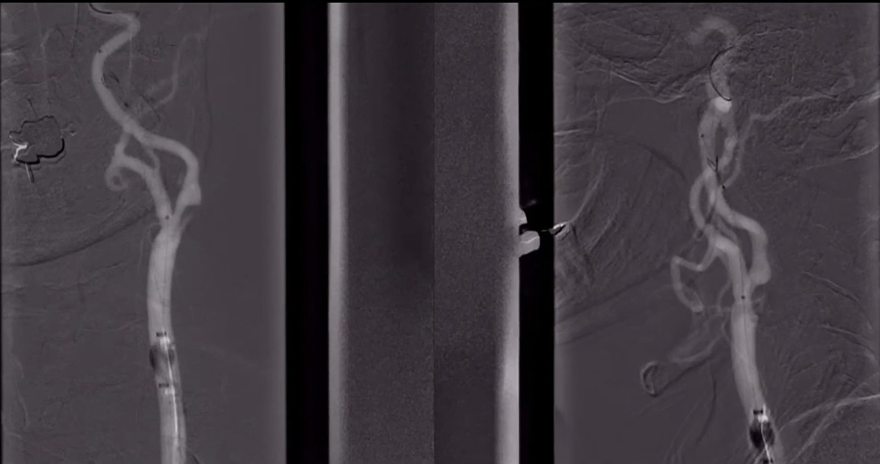

沿保护伞导丝送入4.0mm×30mm球囊,充盈球囊导引导管的球囊阻断血流,于狭窄段定位后命名压扩张球囊,泄球囊时在球囊导引导管的体外端予以负压回抽血液,取出一2mm血栓。经Fluxcap®球囊导引导管输送7.0-10.0mm×40mm自膨支架(Protégé RX)至狭窄段确认位置后释放。应用125cm多功能导管回收保护伞,多功能导管体外端予以负压回抽血液,保护伞内有血栓。

造影可见残余狭窄10%左右,颅内各分支血管通畅。

术后即刻CT:未见明显异常。术后患者症状逐渐好转,出院时NIHSS评分:1分(面瘫1分);继续抗血小板聚集及他汀类药物治疗。